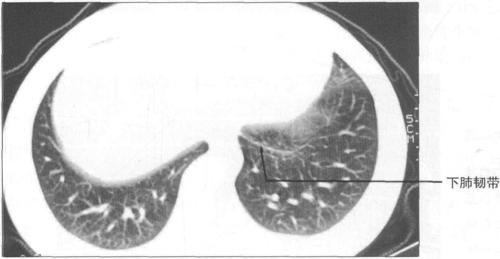

肋膈隐窝(costodiaphragmaticrecesses):肋胸膜与膈胸膜返折形成的半

三,胸部正常ct解剖

胸膜隐窝

肋膈隐窝的位置示意图